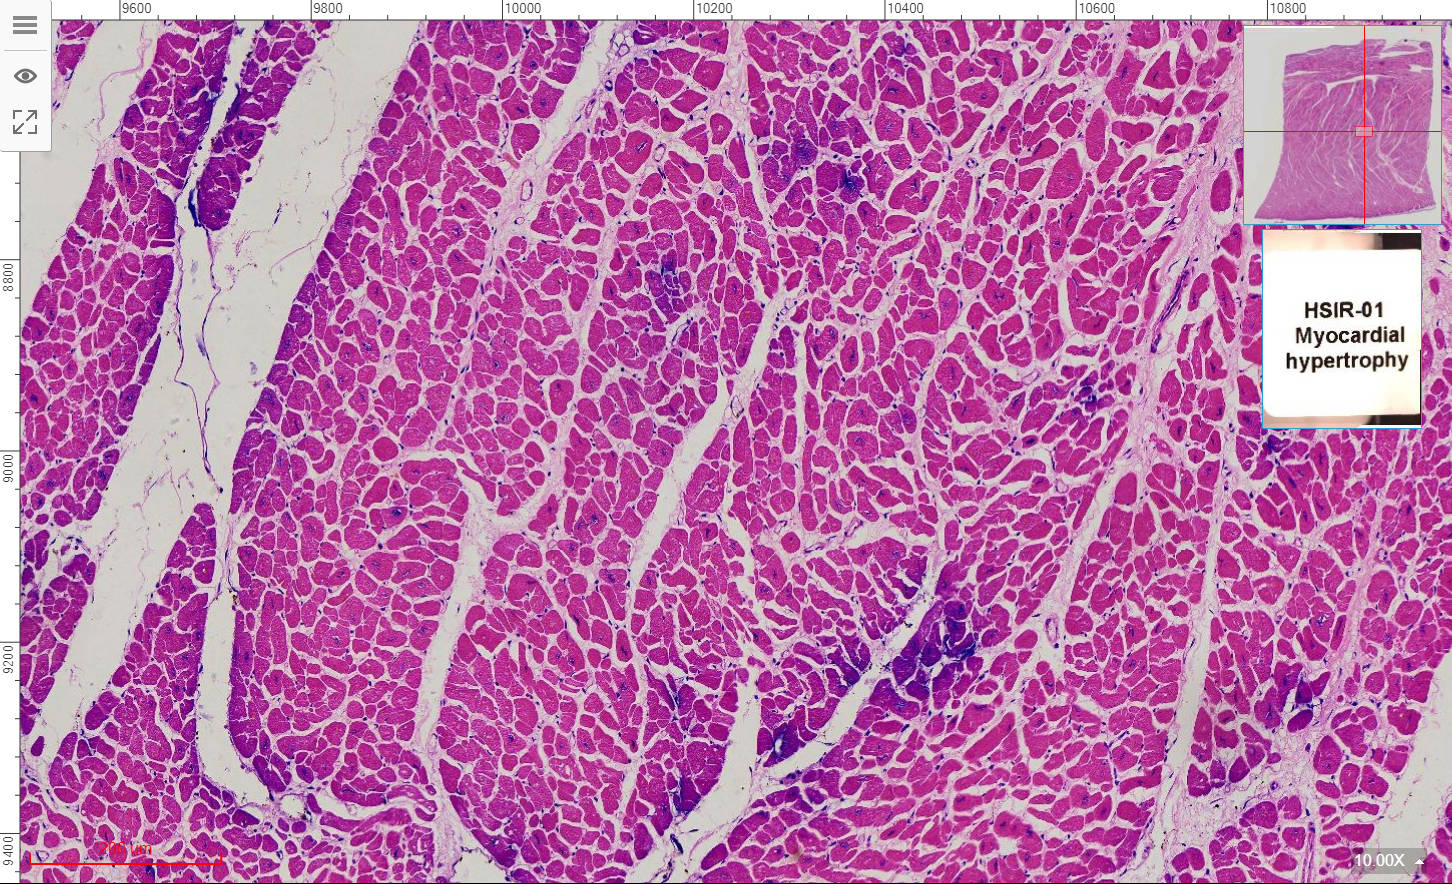

1, Injury and repair of cell and tissue

HSIR-01 Myocardial hypertrophy